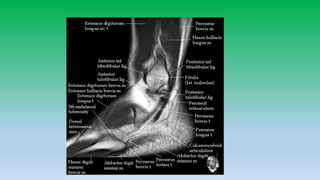

Lateral ankle tendon:

• Peroneus brevis and peroneus longus tendons pass posterior and

inferior to lateral malleolus in the retro-malleolar groove.

• Peroneus brevis is flatter and broader lies anterior to longus, whereas

peroneus longus is posteriolateral and is more rounded. Peroneal

tendons are held inplace by superior retinaculum.

• Split tears are common in brevis.

• Peroneal tendons can sublux or dislocate , whenever there is tear of

superior retinaculum. Diagnosis is made if tendons are located lateral

to distal fibula rather than posterior to it. Hypoplastic retromalleolar

groove can predispose to subluxation.

• 17. Lateral ankle tendon: • Peroneus brevis and peroneus longus tendons pass posterior and inferior to lateral malleolus in the retro-malleolar groove. • Peroneus brevis is flatter and broader lies anterior to longus, whereas peroneus longus is posteriolateral and is more rounded. Peroneal tendons are held inplace by superior retinaculum. • Split tears are common in brevis. • Peroneal tendons can sublux or dislocate , whenever there is tear of superior retinaculum. Diagnosis is made if tendons are located lateral to distal fibula rather than posterior to it. Hypoplastic retromalleolar groove can predispose to subluxation.